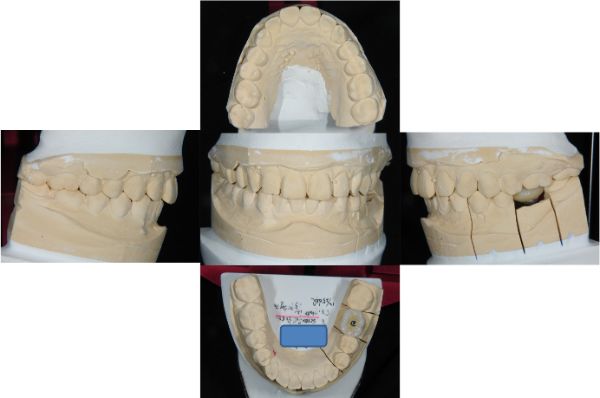

上咬合器製作模型

咬合器製作假牙